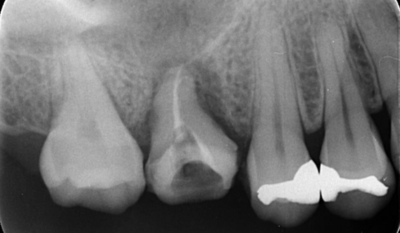

移植手術3ヶ月後のレントゲン画像

移植3ヶ月後。

歯根周囲に透過像を認めるが動揺などはなく、歯周ポケットも形成されていなかった。